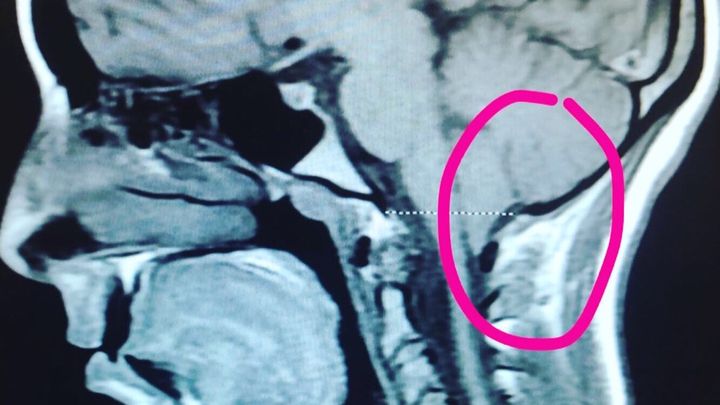

Chiari Malformation is “a problem in which a part of the brain (the cerebellum) at the back of the skull bulges through a normal opening in the skull where it joins the spinal canal. This puts pressure on parts of the brain and spinal cord.” I am scheduled to undergo decompression surgery in September, which happens to be Chiari Awareness Month, to remove the bone at the back of the skull and spine, and open the dura Mater. The dura overlying the cerebral tonsils is opened and a patch is sewn to expand the space, similar to letting out the waistband on a pair of pants. The goals of surgery are “to stop or control the progression of symptoms caused by tonsillar herniation, to relieve compression of the brainstem and spinal cord, and to restore the normal flow of cerebrospinal fluid (CSF).” The surgery takes about 2 to 3 hours and recovery in the hospital usually lasts 2 to 7 days!

Chiari Malformation is “a problem in which a part of the brain (the cerebellum) at the back of the skull bulges through a normal opening in the skull where it joins the spinal canal. This puts pressure on parts of the brain and spinal cord.” I am scheduled to undergo decompression surgery in September, which happens to be Chiari Awareness Month, to remove the bone at the back of the skull and spine, and open the dura Mater. The dura overlying the cerebral tonsils is opened and a patch is sewn to expand the space, similar to letting out the waistband on a pair of pants. The goals of surgery are “to stop or control the progression of symptoms caused by tonsillar herniation, to relieve compression of the brainstem and spinal cord, and to restore the normal flow of cerebrospinal fluid (CSF).” The surgery takes about 2 to 3 hours and recovery in the hospital usually lasts 2 to 7 days!